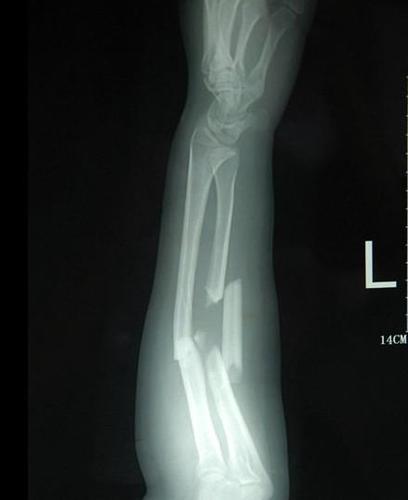

手臂左尺桡骨多段粉碎性骨折